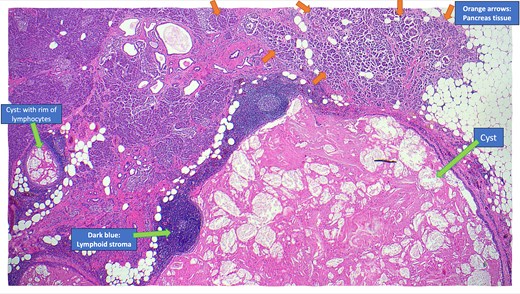

The resected specimen is shown in Fig. 2 and included the distal pancreas and spleen, weighing 202.2 g in total. The pancreas contained a well-circumscribed, lobulated cystic lesion measuring 37 × 27 × 19 mm. The lesion was adjacent to the splenic hilum but did not infiltrate the spleen. The cut surface of the lesion showed multiloculated cystic spaces with tan, necrotic-appearing areas. Histopathological analysis is illustrated in Figs 3 and 4, which confirmed a benign lymphoepithelial cyst. The lesion was clear of all surgical margins, and there was no evidence of malignancy in peri-pancreatic lymph nodes or surrounding tissues.

Annotated haematoxylin and eosin-stained microscopic cross-sectional sample demonstrating atrophic pancreatic parenchyma adjacent to the multilocular cyst with benign lymphoid stroma and reactive lymphoid follicles.

Haematoxylin and eosin-stained microscopic cross-sectional sample demonstrating numerous cholesterol clefts (small left arrows), a band-like rim of lymphocytes (middle large arrows), and the squamous epithelial lining of the cyst wall (medium right arrows).

Pancreatic lymphoepithelial cysts are rare entities with unique histopathological features. They were first described in the literature in 1985 [12]. The mean age of detection is 56 years old, and 80% are found in males [8]. They make up only 0.5% of resected pancreatic cysts, and have been identified in all parts of the pancreas as well as occasionally in extra-pancreatic location [7]. Most patients are asymptomatic, and the lesions are often incidentally discovered on imaging. However, particularly if the cyst is large, patients may present with abdominal pain. The pathogenesis of LECs is unclear but is thought to involve cystic transformation and squamous metaplasia of pancreatic ducts [8]. Radiologically, LECs often mimic more common cystic neoplasms, such as mucinous cystadenomas or pseudocysts. MRI and CT findings, including stable size, lack of enhancement, and absence of pancreatic duct involvement, can favour this diagnosis. However, definitive diagnosis requires histopathological examination, as was necessary in this case. The hallmark of LECs is in their microscopic features, which include unilocular or multilocular cystic structure lined by squamous epithelium, with a cyst wall containing lymphocyte rich cuff with germinal centres [14]. This distinct histology differentiates LECs from other cystic lesions, providing reassurance of their benign nature.